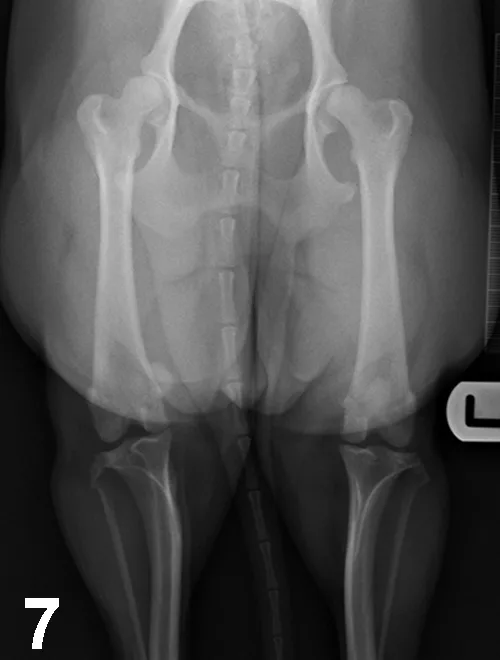

With this developmental disease, coxa vara (ie, decreased angle of inclination of the femoral head) and diminished anteversion angle (ie, less cranially oriented) of the femoral head result in medial displacement of the quadriceps mechanism. This muscular displacement results in abnormal forces that predispose the patella to luxate medially (Figure 7). MPL (95% of cases) is more common than lateral patellar luxation (LPL; 5% of cases); MPL especially affects small-breed dogs, although large-breed dogs may also be affected.1 Patellar luxation can be graded from 1 to 4, depending on the frequency of luxation and difficulty of manual reduction.

Ventrodorsal radiograph of the pelvis and hindlimbs in a 12-month-old Cavalier King Charles spaniel with MPL of the right stifle. Internal rotation of the tibial tuberosity is evident.